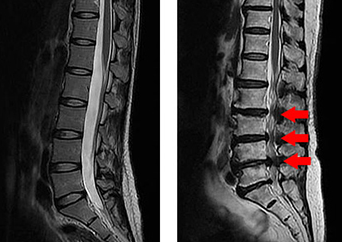

허리 협착증은 척추관이 좁아져 신경을 압박하는 상태를 말합니다. 척추관은 신경이 통과하는 통로로, 나이가 들수록 디스크가 퇴행하거나 뼈와 관절에 변화가 생기면서 척추관이 좁아지게 됩니다. 허리 협착증은 주로 노화로 인해 발생하며, 오래 서 있거나 걸을 때 증상이 악화되며, 심한 경우 앉아있는 동안에도 통증을 호소할 수 있습니다. 따라서, 적절한 치료와 관리를 통해 증상을 완화시키는 것이 중요합니다.